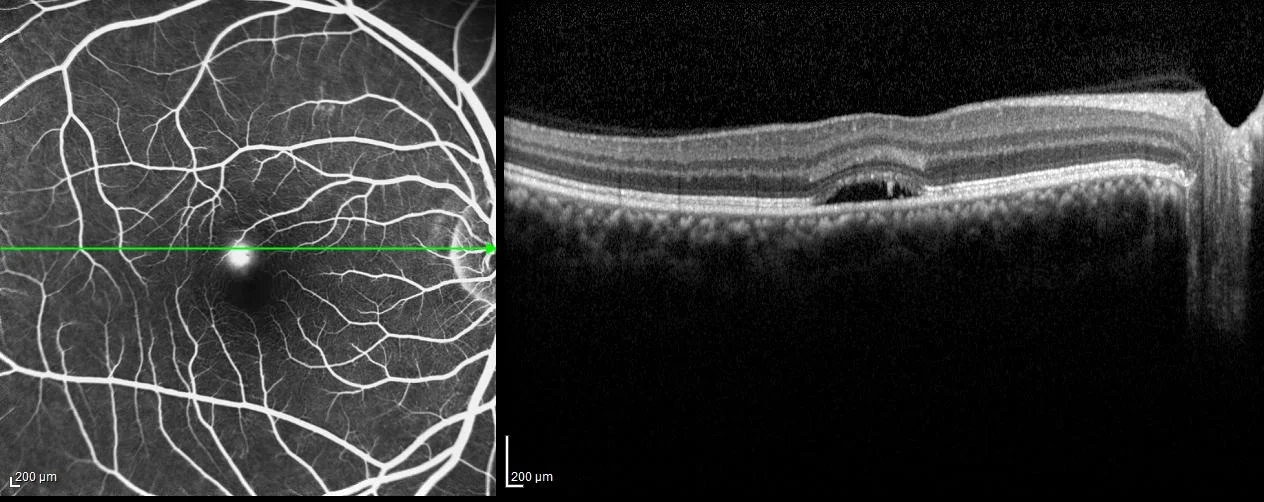

Macular Degeneration

Age Related Macular Degeneration is a chronic disease that can have a sudden impact on vision.  Commonly, this condition is initially mild and undetected by a patient.  The first clinical signs are usually drusen - collection of debris - in the macula (central retina).  This is identified on exam and special imaging.  Patients are often asymptomatic at this stage.  In some patients this condition can progress to advanced disease with metamorphopsia (abnormal waviness of vision) and central vision loss.  The advanced dry form, known as "geographic atrophy," tends to be a slowly progressive disorder that closes in on central vision.  The "wet" macular degeneration features new blood vessel growth that can have devastating changes to vision, sometimes overnight.  Fortunately, we have very effective treatment for the wet form of macular degenration that can stabilize and improve vision in most patients.

Specific eye vitamins are helpful in slowing progression for those with CERTAIN intermediate to advanced findings, and injections can restore vision in many patients with wet macular degeneration.  Earlier treatment is far better than late treatment.   We offer Eylea, Avastin, Lucentis and steroid injections.